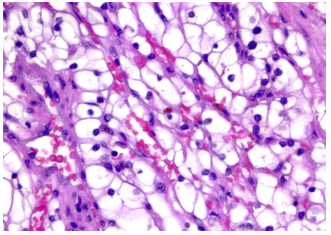

Vi thể

Thường gặp các đám và bè tế bào sắp xếp chặt chẽ, tế bào có bào tương sáng và màng tế bào rõ. Bào tương hạt bắt màu eosin có thể được quan sát trong các khối u độ mô học cao hoặc ở vùng lân cận các ổ xuất huyết hay hoại tử. Hệ thống các mạch máu nhỏ, thành mỏng,phân nhánh dạng cây là một đặc điểm chẩn đoán quan trọng, đặc biệt trong các trường hợp có bào tương hạt eosin. Các kiểu cấu trúc kiến trúc gồm dạng đặc, dạng phế nang hay dạng ổ (alveolar hoặc nested), dạng tuyến nang hay ống (acinar hoặc tubular), dạng vi nang chứa hồng cầu thoát mạch hoặc dịch ái toan, và đôi khi dạng đại nang. Có thể gặp cấu trúc nhú khu trú, tuy nhiên sự hình thành nhú nổi bật làm tăng khả năng các phân nhóm khác như u thận tế bào sáng dạng nhú, ung thư biểu mô tế bào thận có tái sắp xếp TFE3, biến đổi TFEB hoặc đột biến ELOC. Mô đệm thường không đặc hiệu, không có phản ứng xơ sinh, trái ngược với ung thư biểu mô ống góp hoặc ung thư biểu mô niệu mạc, và chỉ có đáp ứng viêm tối thiểu. Các đặc điểm độ mô học cao bao gồm biệt hóa dạng rhabdoid với các tế bào ác tính lớn,độ ác tính cao, bào tương eosin đồng nhất phong phú, nhân lệch tâm và các thể vùi eosin hình cầu trong bào tương, cũng như biệt hóa dạng sarcomatoid, có thể xảy ra ở bất kỳ phân nhóm ung thư biểu mô tế bào thận nào. Hoại tử khối u là một đặc điểm có thể gặp. Các biến thể mô học ít gặp, hiện chưa rõ ý nghĩa tiên lượng,bao gồm dạng nang, dạng giả nhú, tạo xương lạc chỗ, các thể cầu hyaline trong và ngoài tế bào, các thể vùi bào tương bắt màu kiềm, sự hiện diện phong phú của tế bào khổng lồ đa nhân, các u hạt dạng sarcoid hoặc hình ảnh myospherulosis. Ung thư biểu mô tế bào thận tế bào sáng có đột biến BAP1 thường biểu hiện cấu trúc nhú, bào tương eosin và các thể cầu trong bào tương. Trên thực hành, các vùng u độ mô học thấp hơn với hình thái điển hình của ung thư biểu mô tế bào thận tế bào sáng là những vùng hữu ích nhất cho chẩn đoán, trong khi các khối u độ mô học cao hơn có thể biểu hiện các đặc điểm chồng lấp với các тип ung thư biểu mô tế bào thận khác.

Hình 5. ccRCC với hệ thống mạch xoang dạng cây phân nhánh, thành mạch mỏng

Hình 6. ccRCC, có biến đổi vi nang và đại nang, kèm hiện tượng thoát hồng cầu